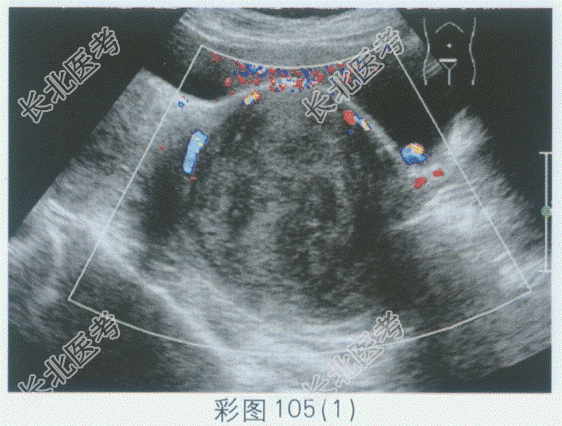

- 单项选择题临床资料:女性患者, 42岁,自述下腹坠胀, 月经量增多3年余。

超声综合描述:子宫前位, 宫颈部可见7.8cm×7.2cm低回声区,边界清晰, 形态规则,内回声不均匀, 呈漩涡状,向外突起, CDFI:周边可见少许血管绕行, 呈动脉血流频谱。见下图及彩图105。

超声提示: A、阔韧带肌瘤

B、子宫颈肌瘤

C、子宫颈妊娠

D、子宫颈癌

E、子宫腺肌病